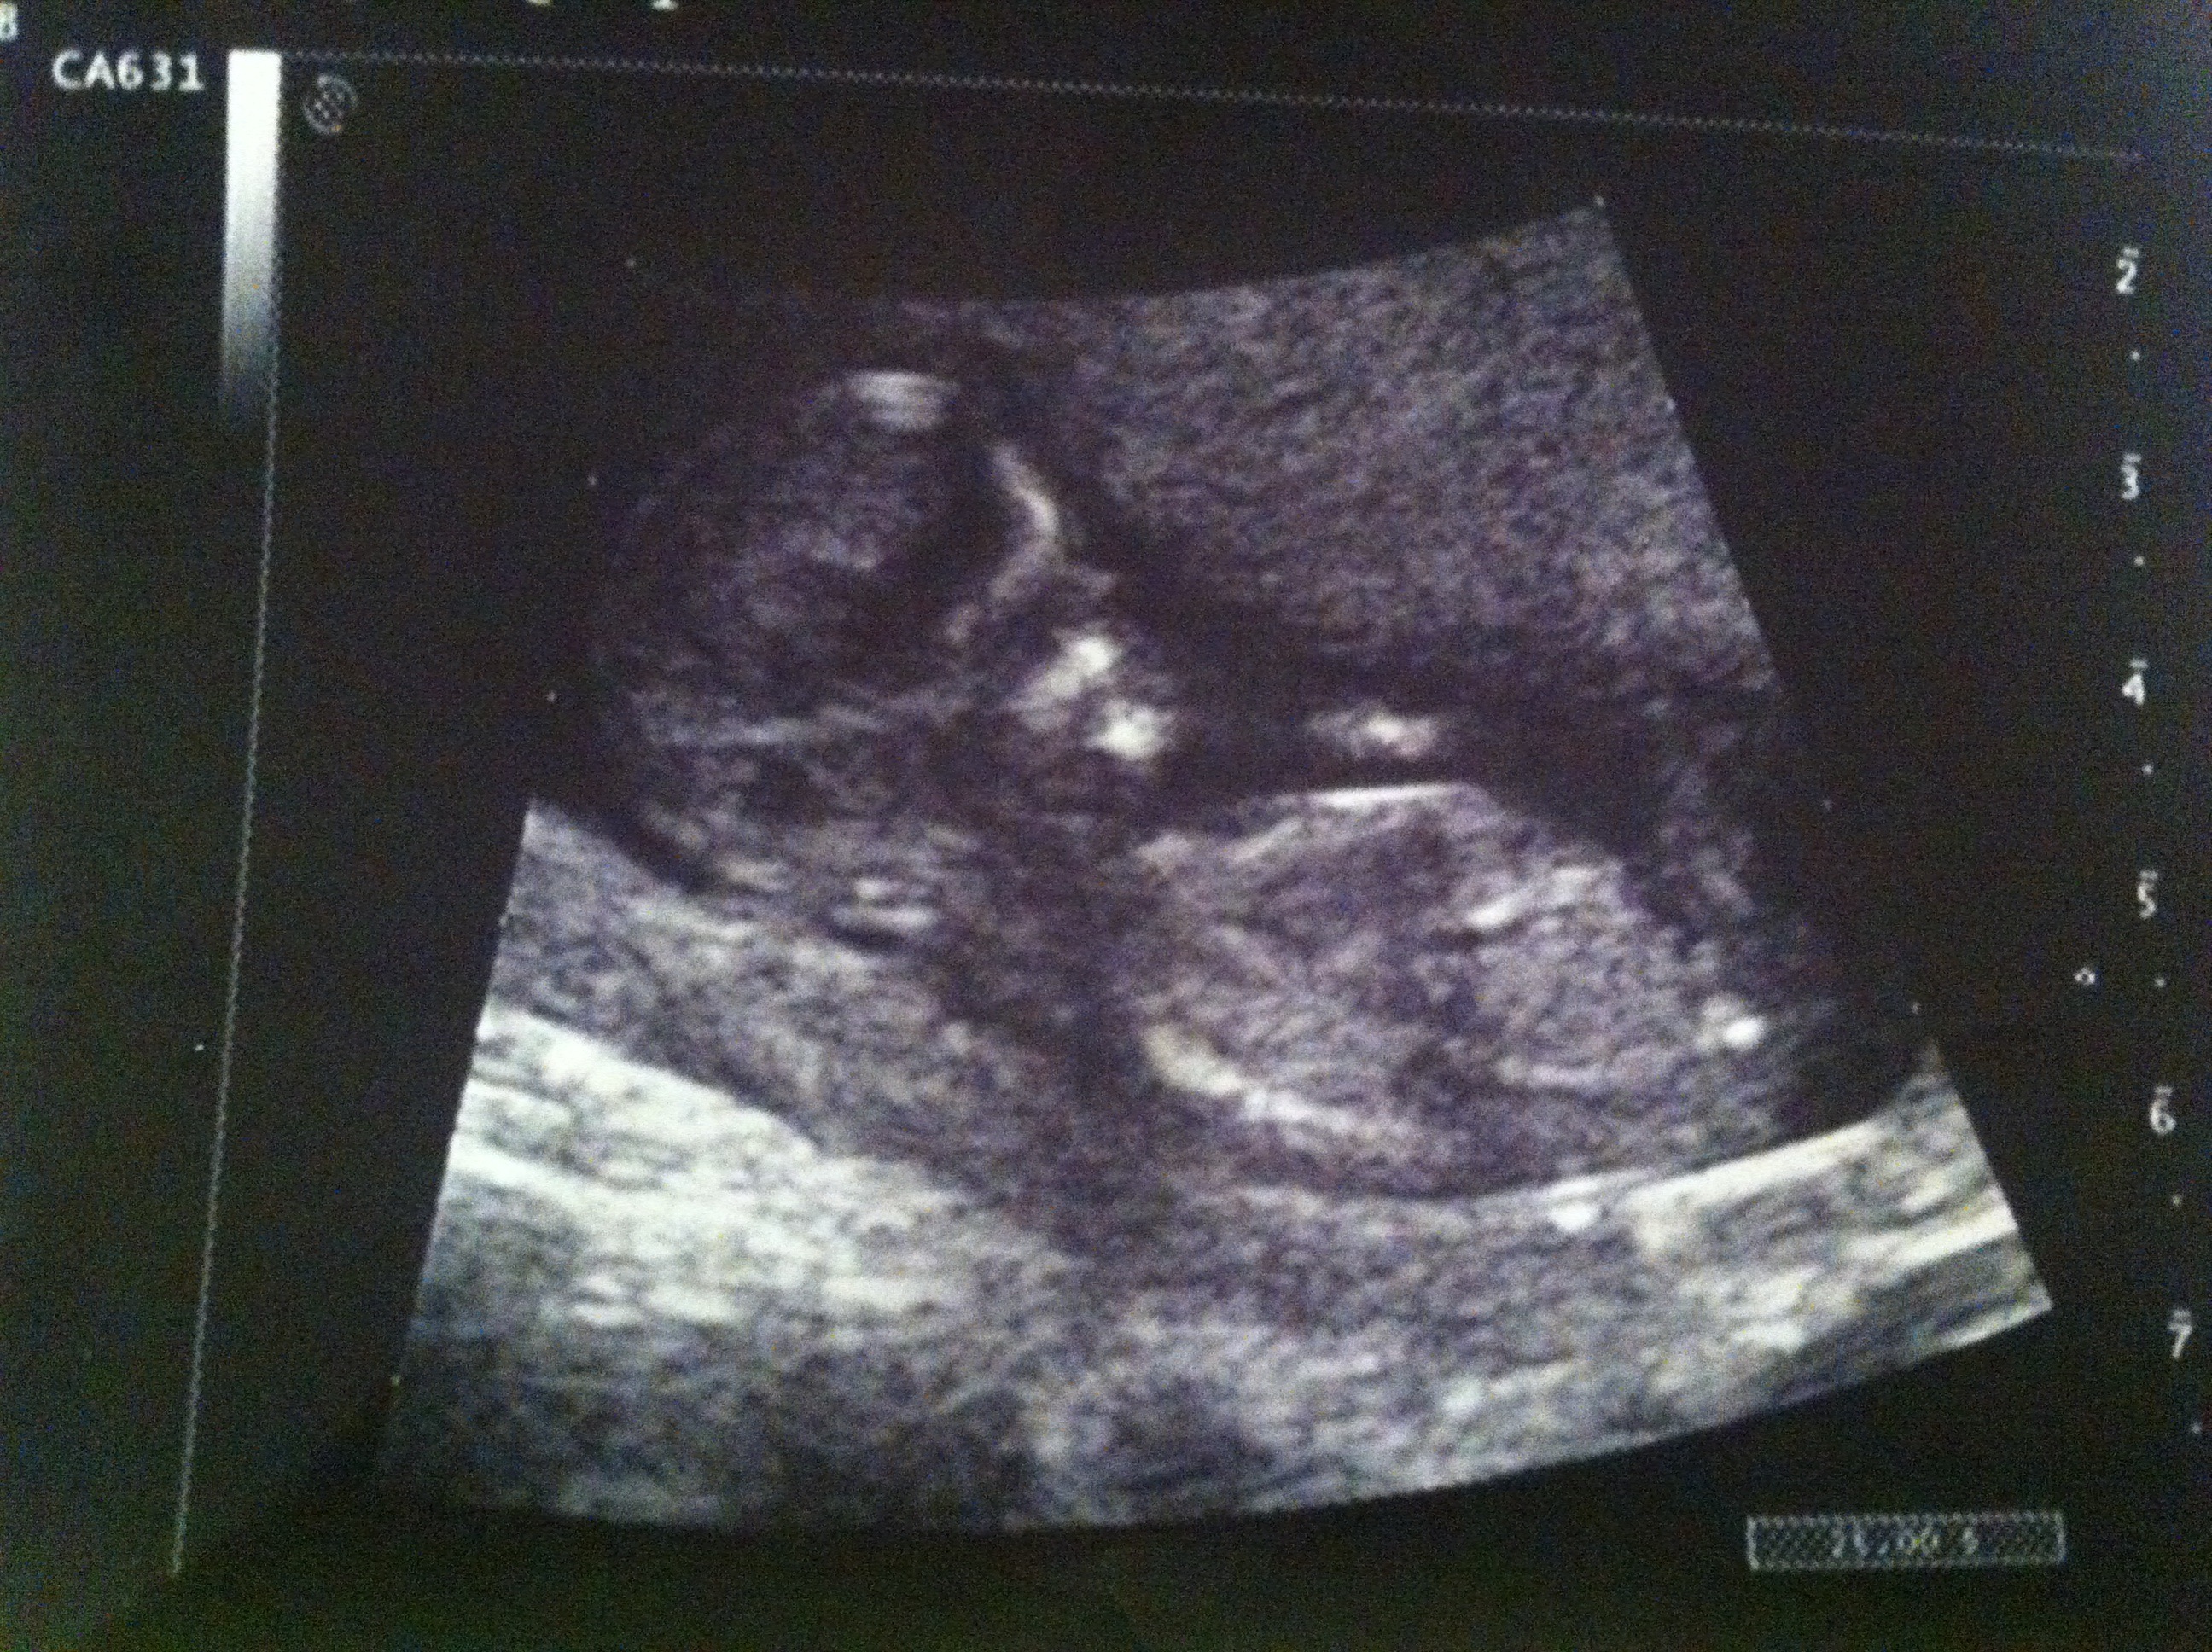

This is my 12w1d ultrasound. The tech was able to tell me confidently the sex of my baby as she said it was quite clear. Can anyone guess? I would love second opinions! Thanks!

Attachment 13868

Almost leaning boy, but is still quite early. What did the technician think it was?

seems your dates might be off, because 12+1 is early and I see a clear upward pointing nub, so I'd say boy!

Yeah i don't see much of any kind of nub, so I say the jury's still out!